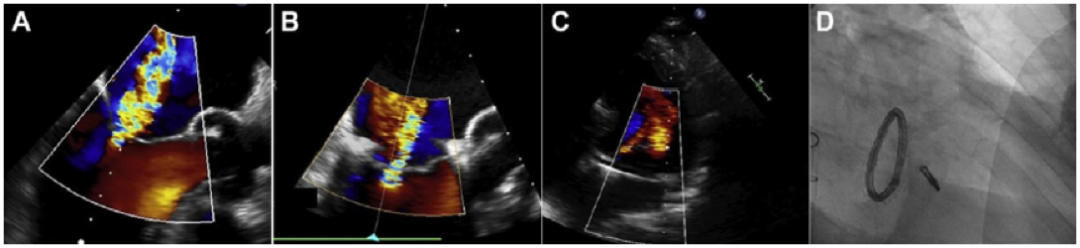

MitraClip于2003年首次植入,是目前使用最广泛的TMVr系统,迄今为止在全球范围内进行了超过150000次手术。MitraClip于2008年首次获得欧盟CE批准,2013年首次获得FDA批准,用于治疗原发性MR和手术风险高的患者,并于2019年3月批准用于治疗中重度或重度继发性MR,尽管存在治疗心力衰竭(GDMT)。受外科Alfieri缝合技术的启发,该导管缘-对-缘修复(TEER)系统最初设计用于通过使用一个或多个聚酯包覆的钴铬双臂夹子连接二尖瓣(MV)前叶和后叶的自由边缘来创建双孔(图5A)。MitraClip输送系统通过股静脉引入,带有一根可操作的24F引导导管(图5B),通过穿刺房间隔进入左心房(LA)。然后,夹子输送系统穿过导向鞘,夹子打开并定向,然后进入左心室(LV)。在经食道超声心动图(TEE)和透视引导下,导管被撤回,瓣叶自由边缘被抓住,从而MR减少(图6)。在释放之前,器械可以重新打开和重新定位,直到达到最佳效果。

图6。(A,从左至右)透视和经食管超声心动图(TEE)图像显示经中隔穿刺后左心房(LA)内导管;

彩色多普勒经食管超声心动图(TEE)图像显示重度MR(B,从左到右)透视检查,彩色多普勒,以及三维经食管超声心动图(TEE)图像显示左心房(LA)中的片段。

(C,从左至右)透视和经食管超声心动图(TEE)图像显示,抓取瓣叶后,左心室(LV)中的夹子闭合;经食管超声心动图(TEE)图像显示二尖瓣平均压差为1毫米汞柱。

(D,从左到右)显示Clip释放的透视图像;彩色多普勒和三维经食管超声心动图(TEE)图像在手术结束时显示轻度MR。

LA:左心房;MR:二尖瓣返流;TEE:经食管超声心动图。